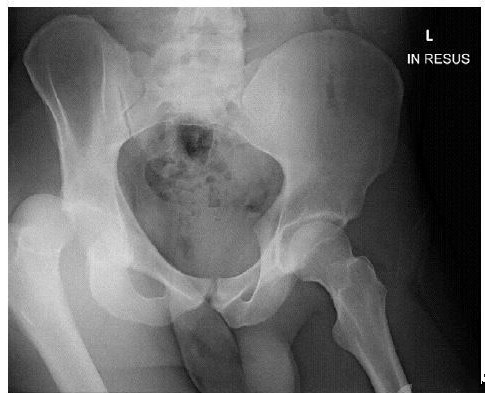

经典病例_创伤性髋关节后脱位致股神经麻痹_